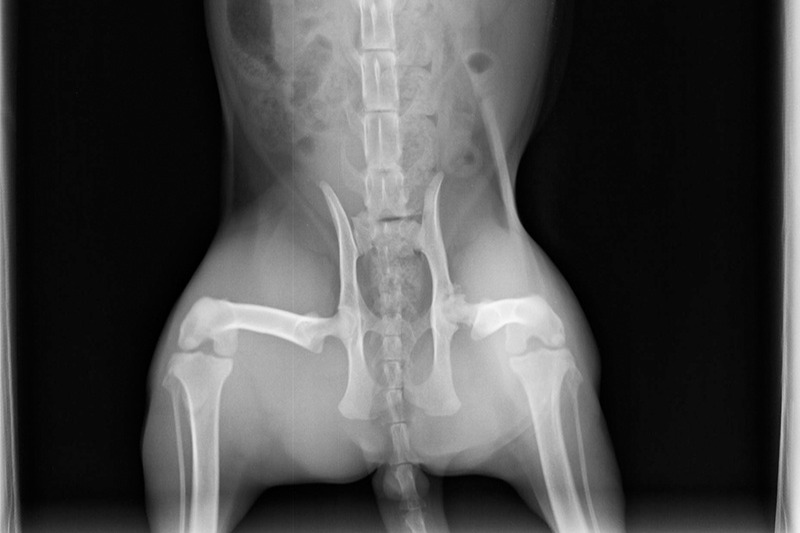

When I took him back to the vet for his booster shots, I asked them to X-Ray his hip to see if it was an injury or a congenital condition. They gave me the bad news that it was a defect in his hip which was going to keep getting worse until it could be corrected with surgery. I could afford a couple of hundred dollars here and there for normal vet expenses, but I'm a gig worker, and COVID took all my gigs away. There was no way I was going to be able to come up with a few thousand any time soon. Now, several months have gone by, and Ziggy no longer follows me around the house. The poor little guy can barely walk anymore, and although I have finally started getting work again in the last few weeks, I am nowhere near on an even keel yet, and Ziggy can't wait any longer.

Below are Ziggy's X-Rays- The first set was taken when I first got him in October. The others were taken three months later. I don't really know how to read them, but the vet said they could see noticeable deterioration in that short time: